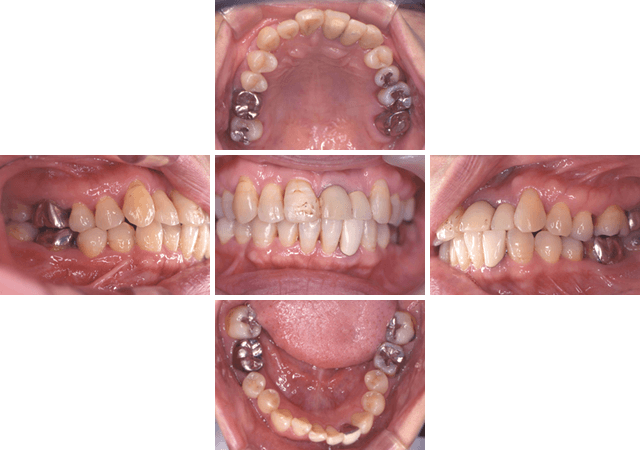

50代 女性

エムドゲインを使用した歯周治療

| 主な症状 | 全体的にしみ、歯茎が下がってきた。 |

| 口腔内の状況 | 全顎的に歯石が多量に沈着しており、腫脹や発赤もみられる。中等度から重度の歯周炎。 |